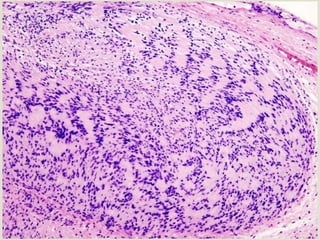

 Nodular mass of fibrous connective tissue covered with

stratified squamous epithelium

 Non-encapsulated lesion; fibrous tissue blends into the

surrounding connective tissue

 CONNECTIVE TISSUE

 Dense and collagenized; scattered inflammation

 Collagen fibres are arranged in radiating, circular or

haphazard pattern

 EPITHELIUM

 Atrophy;flat rete ridges or thin and elongated rete

ridges

 Sometimes hyperkeratosis (clinically white)

FIBROMA

Histopathology